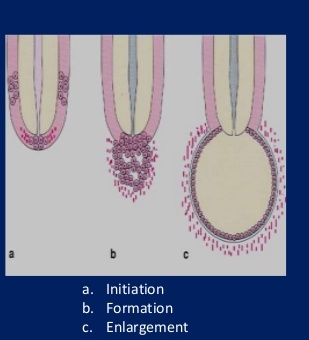

Mechanism of cyst formation :

- Proliferation of the epithelial lining

- Food regulation within the cyst cavity

- Bone resorption

Mechanism of cyst formation Proliferation of the epithelial lining Fluid accumulation within the cyst cavity Bone resorption : Epithelial cysts A) Odontogenic cysts. 1) Developmental odontogenic cysts

PATHOGENESIS THREE STAGES

1. Cyst initiation

2. Formation 3. Cyst enlargement or expansion